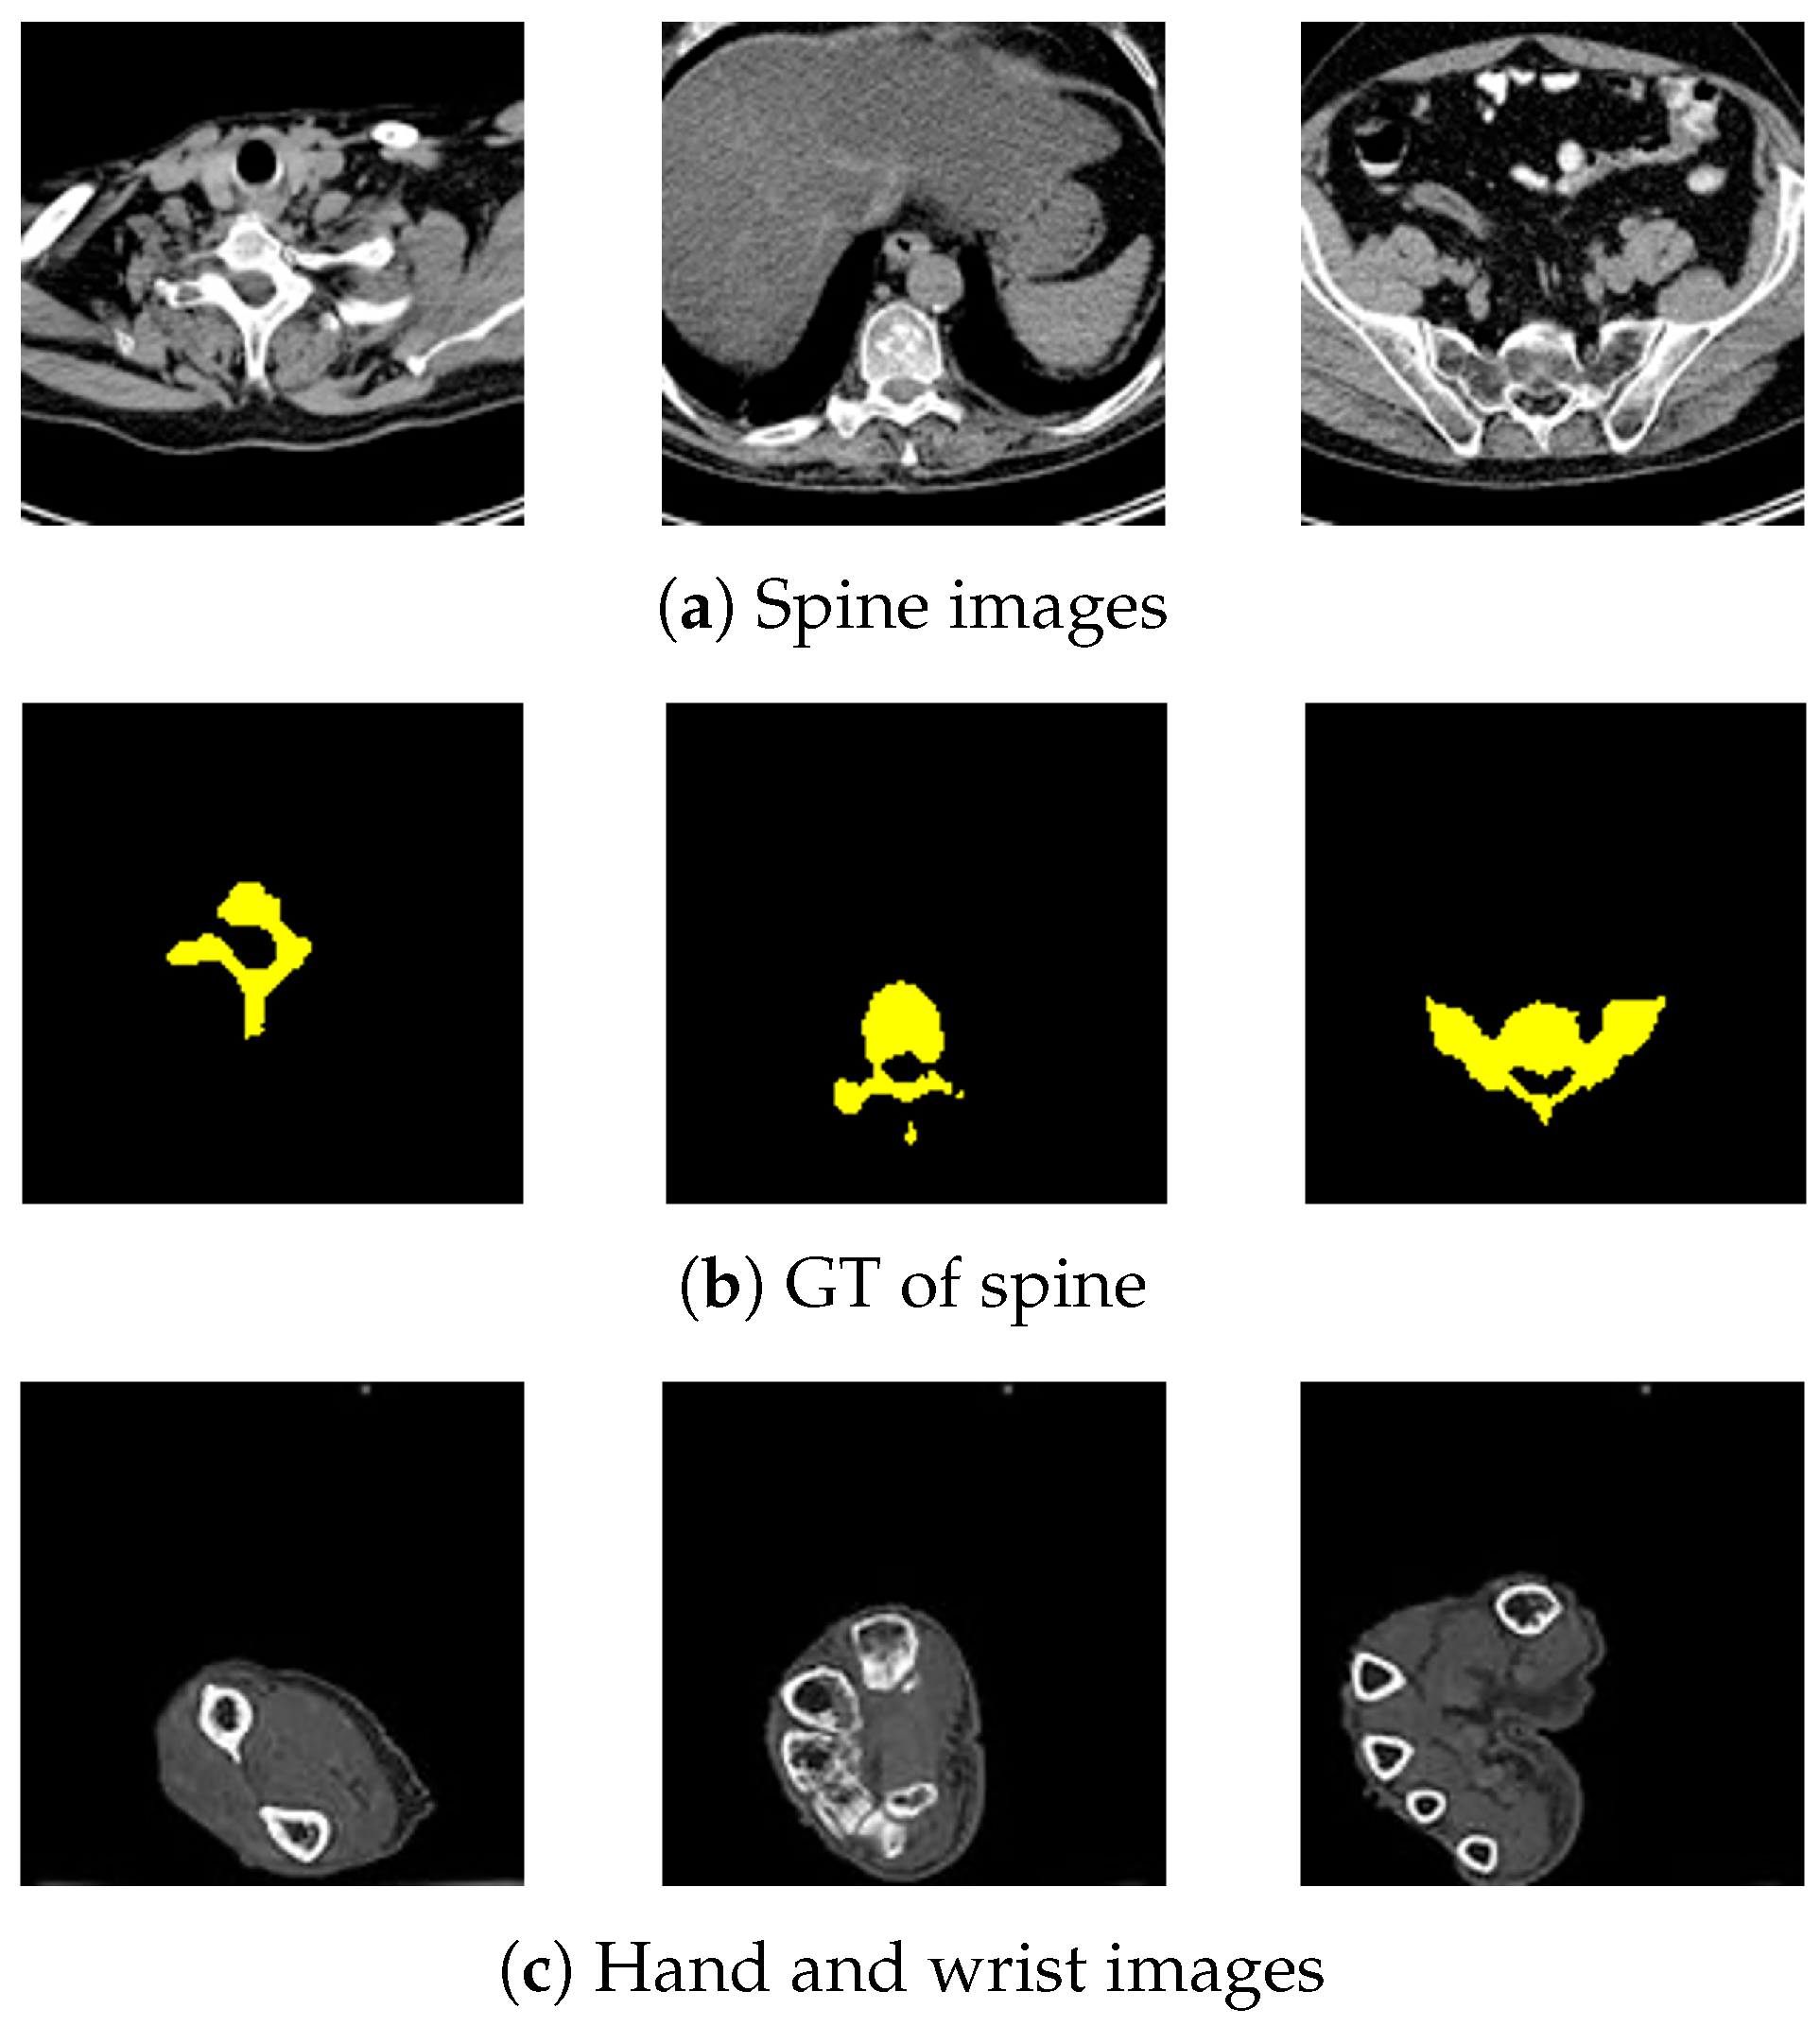

Examples of spine, hand, wrist, and femur images and ground truth (GT) are shown in Figure A1. The spine dataset used in this experiment ranged from the neck to the tailbone. The femur dataset used in this experiment ranged from the coxa to the knee. The range of the hand and wrist dataset was from the fingertips to the elbow. The GTs for the spine and femur were verified by an experienced person with over 3 years of experience. The hand and wrist GTs were created by orthopedic surgeons to set the ROI. A total of 276 spine images were divided into three sets with a ratio of 8:1:1 for training, testing, and validation. The spine dataset was augmented to three times the number of pictures using Gaussian noise. This brought the number of spine datasets to 828 images. A total of 186 femur images were also applied to the same data augmentation and dividing. In addition, 472 hand and wrist images were used as training images, and 373 images from another patient were used as test images. The hand and wrist dataset was increased by a factor of 4 using CT images of the hand and wrist taken from four different angles, so it contained 1884 images. These images size was 256 × 256 [px].

Figure A1.

Datasets.